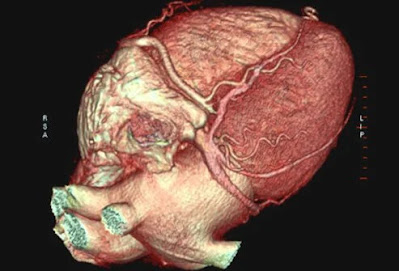

Έλεγχος καρδιακών παθήσεων: Καρδιακή τομογραφία

Μια αξονική τομογραφία καρδιάς δείχνει συσσώρευση ασβεστίου στις στεφανιαίες αρτηρίες για εκείνους που διατρέχουν αυξημένο κίνδυνο καρδιακών παθήσεων και καρδιακής προσβολής.

Η εξειδικευμένη καρδιογραφική τομογραφία (CT) ή «καρδιακή αξονική τομογραφία» μπορεί να παρέχει λεπτομερείς τρισδιάστατες εικόνες της καρδιάς. Οι εικόνες μπορούν να χειριστούν για να αναζητήσουν συσσώρευση ασβεστίου (πλάκα) στις στεφανιαίες αρτηρίες ή να παρέχουν εικόνες τέτοιων εσωτερικών δομών της καρδιάς όπως βαλβίδες ή πάχος τοιχώματος.

Οι αξονικές τομογραφίες μπορούν επίσης να χρησιμοποιηθούν για την εξέταση φυσιολογικής ανατομίας της καρδιάς ή συγγενών ελαττωμάτων. Οι πληροφορίες από έναν αξονικό τομογράφο μπορούν να δώσουν εικόνα για διάφορα προβλήματα καρδιακών παθήσεων.